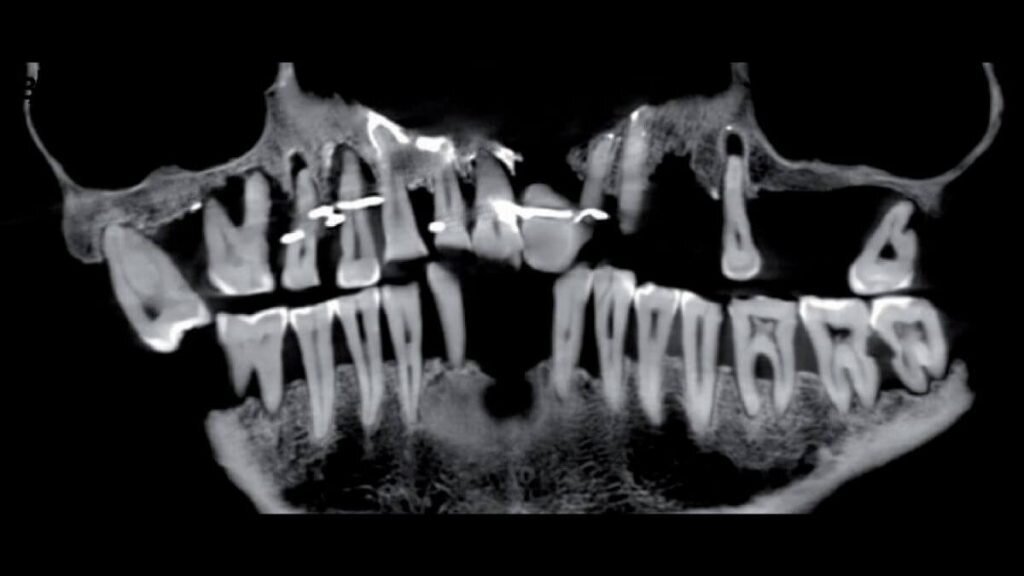

Рентгеновский снимок зубов Анны д’Алегр

Коллетер является ведущим автором нового исследования зубов Анны д’Алегр, опубликованного 24 января в Journal of Archaeological Science: Reports. Реанализ останков включал в себя сканирование черепа с помощью «конического луча», который использует рентгеновские лучи для создания трехмерного изображения. Это сканирование показало, что д’Алегр страдала от серьезного заболевания пародонта, из-за которого многие ее зубы расшатались, и что ей вставили тонкие золотые проволоки, чтобы зубы не выпадали.

Часто провода обматывались вокруг нижней части зубов д’Алегр возле десен. Но некоторые из ее зубов были проколоты для прохождения проводов, и у нее также был вставной зуб, сделанный из бивня слона.